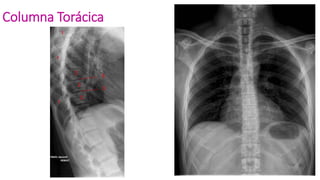

Columna Torácica

Columna

Lumbosacra